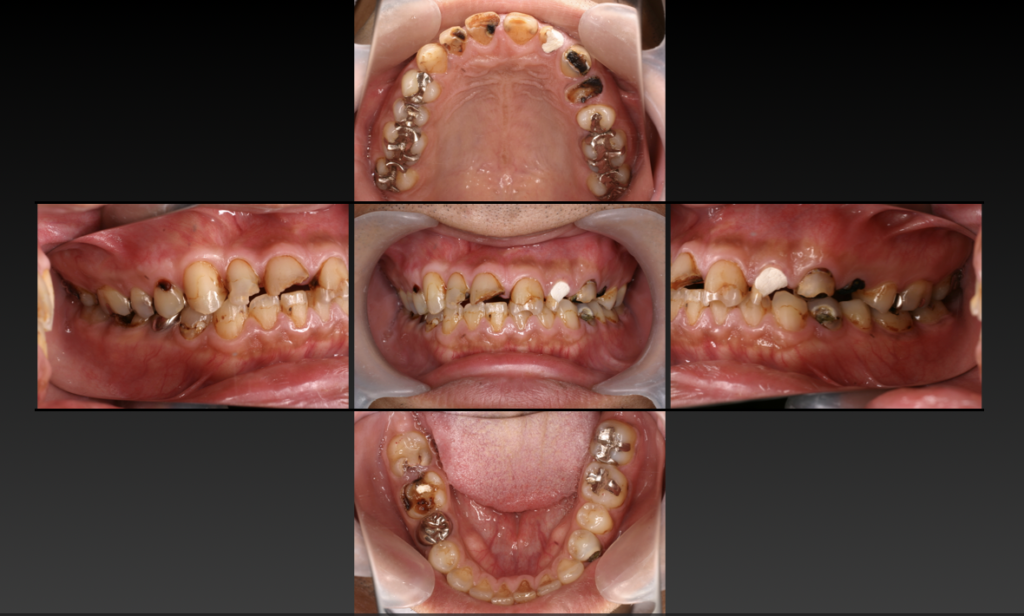

う蝕による咬合崩壊 全顎治療

| 治療方法 | 食生活、生活習慣の乱れからの虫歯による咬合崩壊症例 全体的な歯周治療、プラスチックの治療用の歯による咬合治療後、コンポジットレジンとセラミックによる咬合再構成。 咬合治療とはお口の中をひとつの単位と捉え、咬み合わせや審美性、顎関節などをトータルに治療していきます。口腔内の崩壊をきたしてしまった患者さんに対して、悪くなってしまった原因を追求し、次は悪くならないように、機能面、清掃性、審美性のトータル治療が「全顎治療(フルマウスリコンストラクション)」です。虫歯や歯周病になってしまった歯を1本だけ治すのではなく、お口全体を考慮して長期的な視野に立った健康維持を行うために治療計画を立てていきます。 劇的なスマイルの改善、食生活も見直していただき肌つやも良くなりお顔の印象が大きく変化しました。公私ともに周囲の評価も上がったと非常に喜んでいただきました。 虫歯だから詰めて終わるのではなく、なぜ虫歯になったのかを追求し歯科治療にあたりました。 |